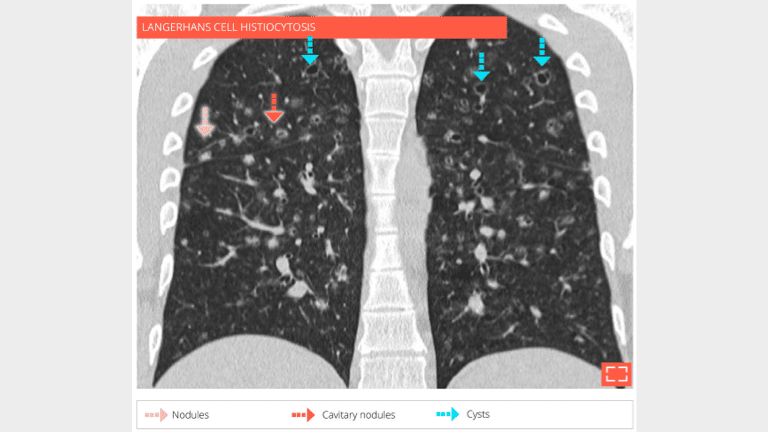

The patient is a 28-year-old male, smoker, with langerhans cell histiocytosis. HRCT at the level of middle zone shows bilateral and symetrical abnormalities of the lung parenclyma consisting in nodules, cavitated nodules, and cysts.